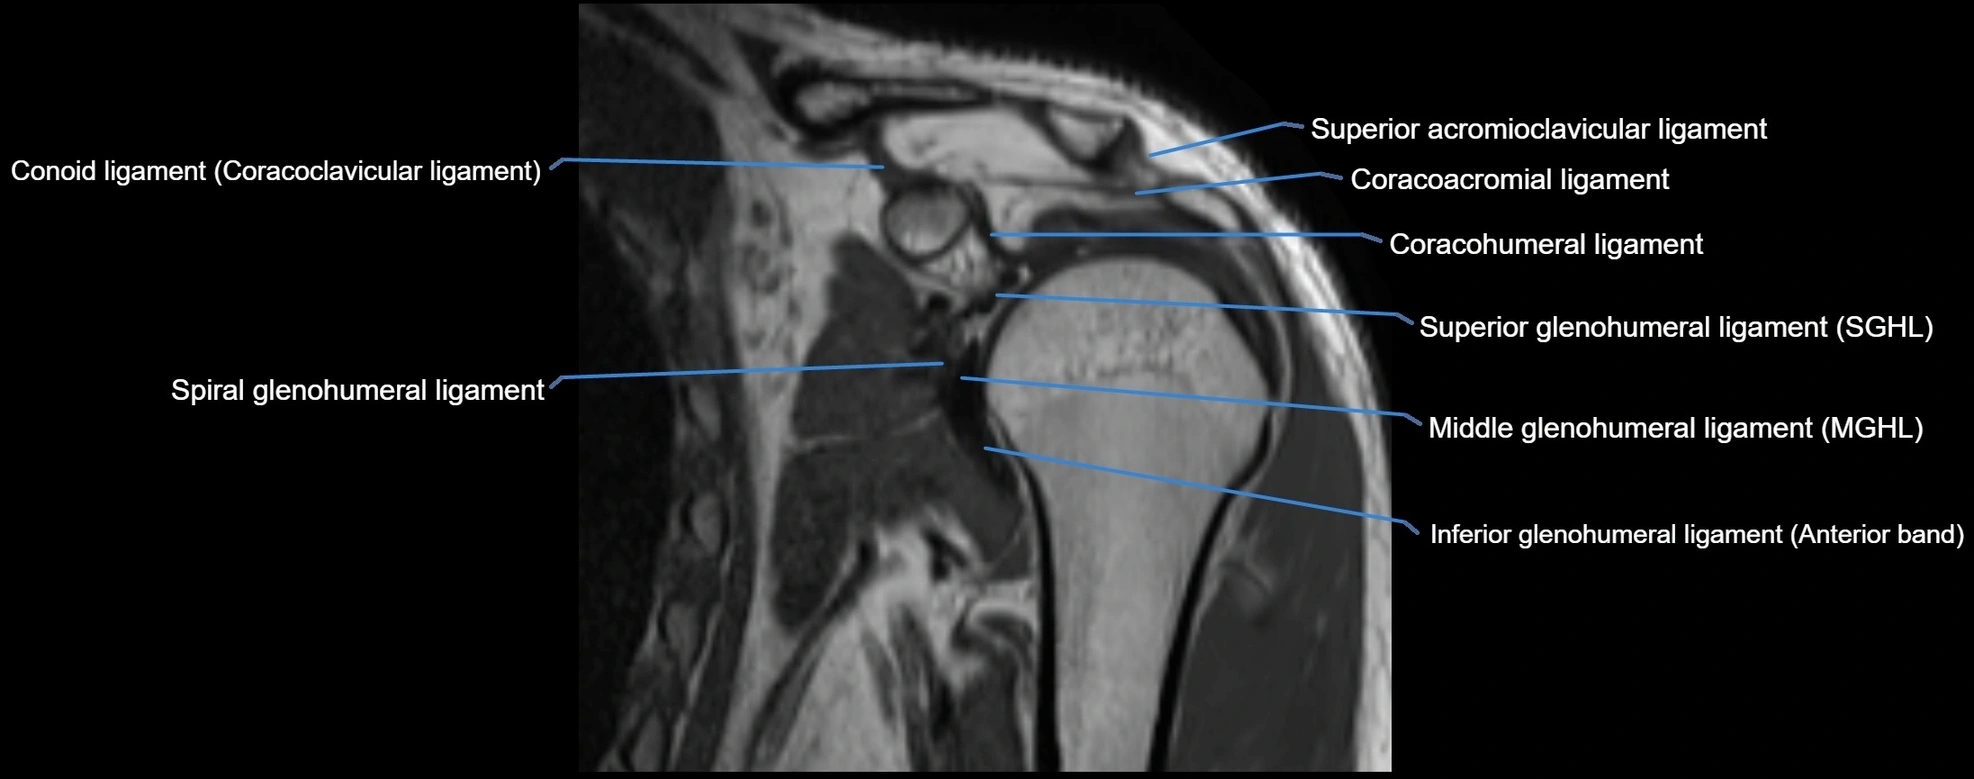

MRI Appearance

• T1-weighted images:

• Normal ligament: Low signal (dark linear band) spanning acromion to clavicle.

• Surrounding fat planes: Bright, delineating the ligament clearly.

• Marrow of clavicle and acromion: Bright due to fatty content.

• Tears: Discontinuity or irregular thickening with intermediate-to-bright signal.

• Chronic injury: Thinning, fraying, or irregular low-signal fibers with adjacent scarring.

• T2-weighted images:

• Normal ligament: Low signal, homogeneous.

• Partial tear or sprain: Focal hyperintensity or thickening.

• Complete tear: Discontinuity with fluid-bright gap between clavicle and acromion.

• Associated edema: Bright signal in distal clavicle or acromion marrow.

MRI images

image